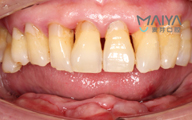

但是打完麻药,躺在那里发现手术时一点感觉也没有,半口牙只种了5颗牙钉,而且不到一个小时,感觉自己就眯了一会就好了。麦芽的种植专家们手法特别棒,很稳。牙钉种好之后,没有立即戴牙冠,医生用硅橡胶取模,为我制作了临时牙冠,不过看到临时牙冠我就能想象到完全种好牙的样子了!然后,医生给我一个小卡片,上面记录了种牙后的注意事项,告诉我种完牙后自己维护也很重要。医生说要按时复诊,也会有专门的工作人员进行通知,不得不说麦芽在细节上真的很暖心。

我种牙后并没有什么不适,下牙的牙齿种好了,我又找麦芽的硕博专家把上牙的几颗牙齿也种了,绝对不能因为一颗坏牙再引发其他的口腔问题。临时牙冠佩戴没有任何不适,做了永久修复,而且麦芽的硕博专家还给我分析下牙和上牙的咬合关系,不能随便就戴牙冠,种的好是一方面,更重要的是咬合和使用功能。